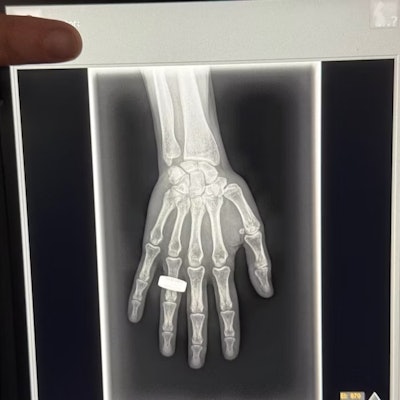

The first finalist for Best Radiology Image is out of this world — literally, it is the first x-ray taken in space.

The image was acquired during the Fram2 space mission led by 42-year-old cryptocurrency entrepreneur Chun Wang. The mission launched on March 31 from NASA’s Kennedy Space Center in Florida. On April 1, the all-civilian crew woke up, had breakfast, and “took a few x-ray images,” Wang wrote in a post on the social media platform X.

Image from an X post by @satofishi.

Sharp observers will note that the image bears a resemblance to the first x-ray ever taken by Wilhelm Roentgen of his wife Anna Bertha Ludwig’s hand on December 22, 1895.

That was intentional.

“The crew members were informed of Wilhelm Roentgen’s first x-ray image and were excited to honor that pioneering achievement 129 years later by recreating the image in space,” said Jeanne Walter, vice president of marketing and sales for MinXray, the company that manufactured the portable x-ray machine used to acquire the image.

An analysis of the acquired data and images is still underway, and findings will be shared once the research is complete, Walter added.